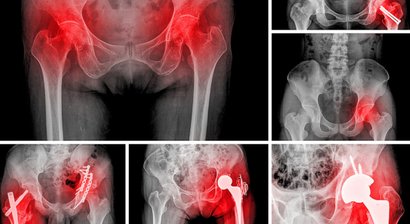

Hüftprothese

Bei Patienten mit stark fortgeschrittener Arthrose im Bereich der Hüftgelenke, bei welchen konservative Behandlungsmethoden nicht mehr wirksam sind, wird die Implantation einer Hüftprothese notwendig, mithilfe welcher das Hüftgelenk wieder in einen Zustand der Schmerzfreiheit und Bela...